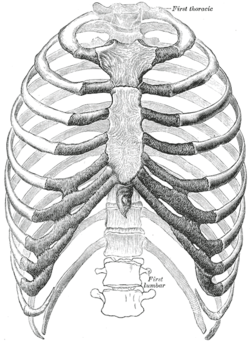

Pošto prsni koš zauzima veliki dio tijela, on ima istureni položaj i često je sklona ozljedama. Tijekom tih ozljeda, rebra su najviše izložena ozljedama, pa i prijelomima. Kod mlađih osoba, zahvaljujući elastičnosti rebara, pojava je prijeloma znatno rjeđa nego kod starijih osoba, kod kojih osim zakrečenosti hrskavice nastaje i staračka osteoporoza.

Kako je središnji dio prsnoga koša najistureniji, najčešće se prijelomi rebara javljaju kod srednjih rebara, a najrjeđe kod gornja tri, koja su na izvjestan način zaklonjena ključnom kosti. Lokalizacija prijeloma je najčešća na prednjim ili zadnjim zavojima, a prouzročena je izravnim (direktnim) ili posrednim (indirektnim) djelovanjem sile.